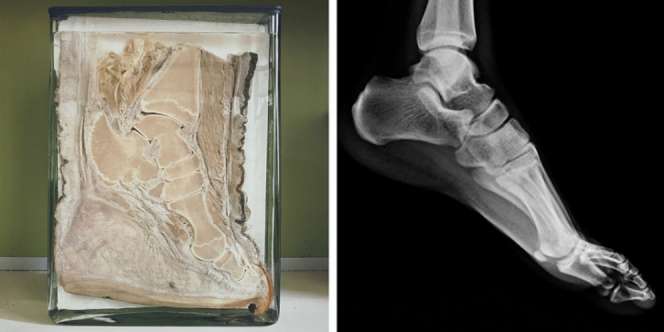

1. Ini adalah kaki dari hewan Platypus.

10. Tulang kaki gajah dan manusia hampir tak ada perbedaan